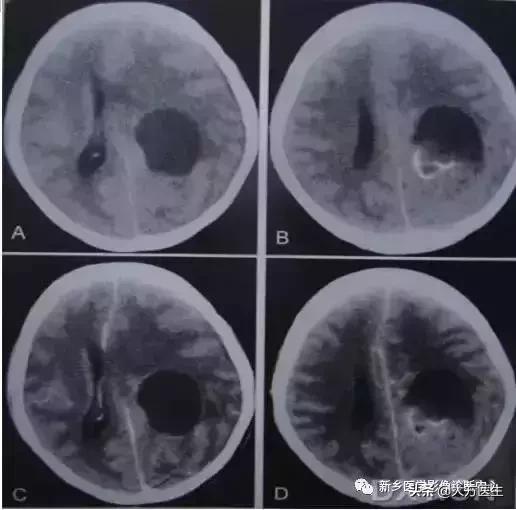

17、转移瘤

转多瘤钙化罕见,主要为骨肉瘤和乳癌转移,也可见于肺癌转移。

左2为肺癌转移,右1为乳癌转移